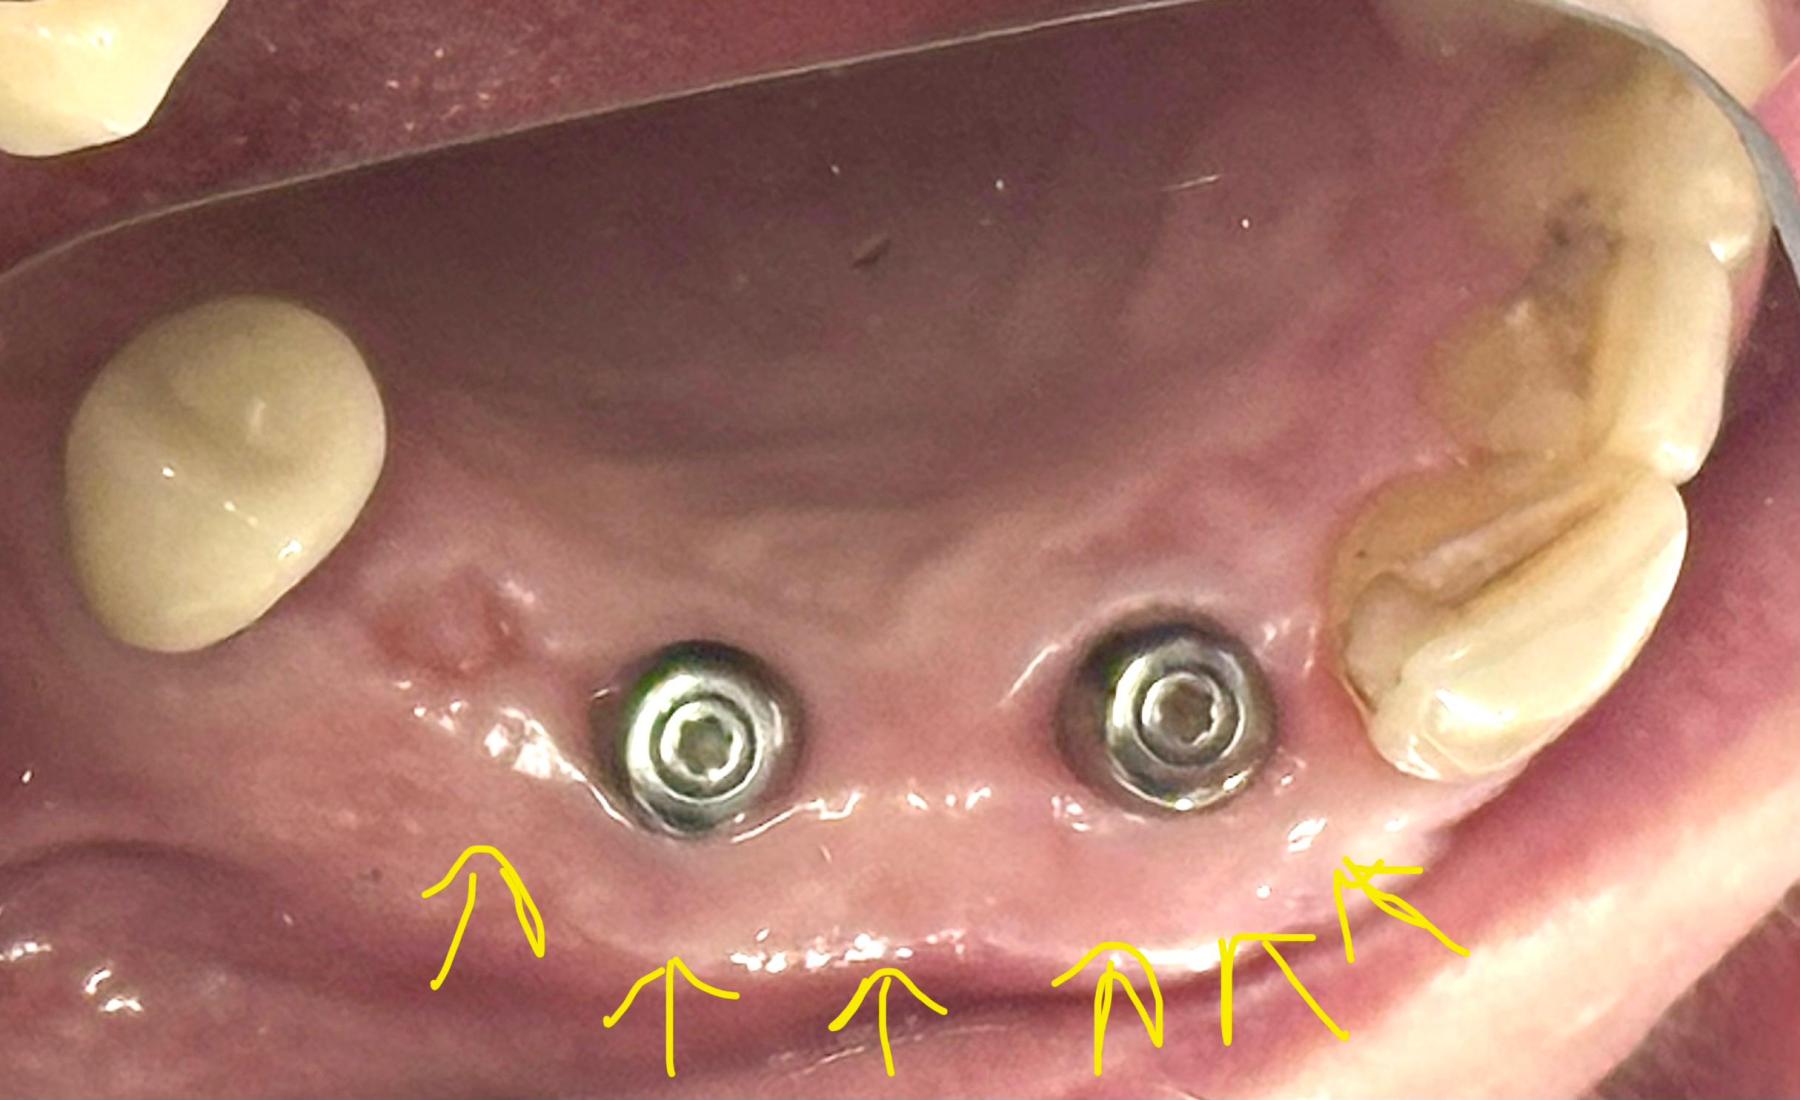

Implants placed using a digitally planned stackable surgical guide following alveolectomy, ensuring ideal positioning and a stable foundation for full-arch restoration.